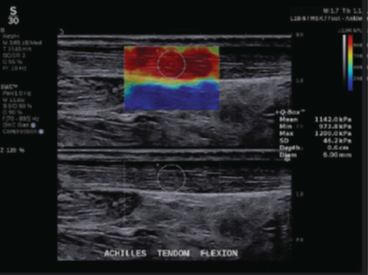

(2)進化したSWE PLUS™イメージング

従来システムではSWEのレンジは800 kPaまででしたが、SUPERSONIC™ MACHシリーズでは、最大1200 kPaまで測定が可能*となっています。

*MSKプリセット使用時

整形領域では腱や筋肉の硬さ、乳腺領域では腫瘍の硬さ、肝臓領域では、肝組織の硬さを評価することで、疾患の早期診断に貢献します。